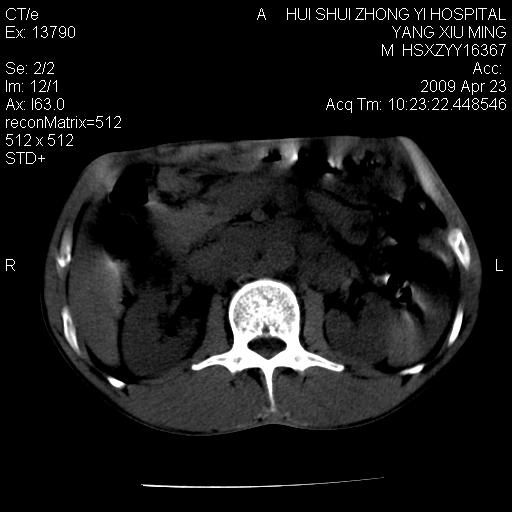

上腹部疼痛一月,呕吐10天,发现左侧颈部包快10天 胸部cr片未见明显异常。

腹膜后淋巴结增大,转移、淋巴瘤?胰腺增大,胰腺炎?占位?颈部考虑增大淋巴结。建议腹部增强扫描。

缺少强化资料,暂考虑胰腺癌广泛转移.

黑!广泛淋巴结肿大不符合胰腺癌转移。胰腺周围淋巴结肿大致使胰腺看起来大。考虑淋巴瘤可能大。